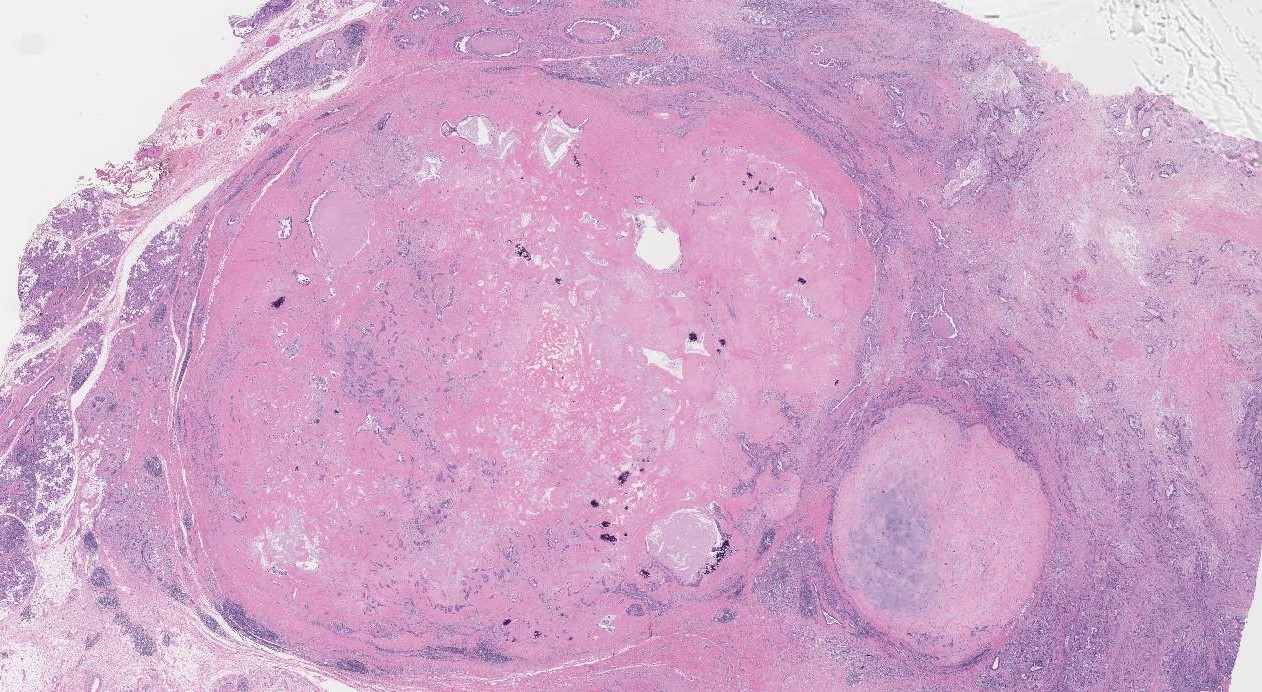

多形性腺腫由来癌 (CXPA) は、まれなタイプの唾液腺癌です。手術と放射線療法が最も一般的な治療選択肢です。

CXPAは、多形腺腫と呼ばれる非癌性腫瘍から発生します。多形性腺腫は最も一般的なタイプの唾液腺腫瘍です。これらの腫瘍のうち CXPA になるのはほんのわずかです。

CXPA はまれであり、ほとんど理解されていませんが、多形性腺腫と呼ばれる良性腫瘍から発生します。多形性腺腫は以下から構成されていると考えられています 45%~75%唾液腺腫瘍のこと。このうち CXPA になるのはほんのわずかです。

CXPAを他の種類の唾液腫瘍と区別するには、細針吸引が必要です。組織サンプルは研究室に送られ、医師は細胞の種類と特定の遺伝子マーカーを調べることができます。